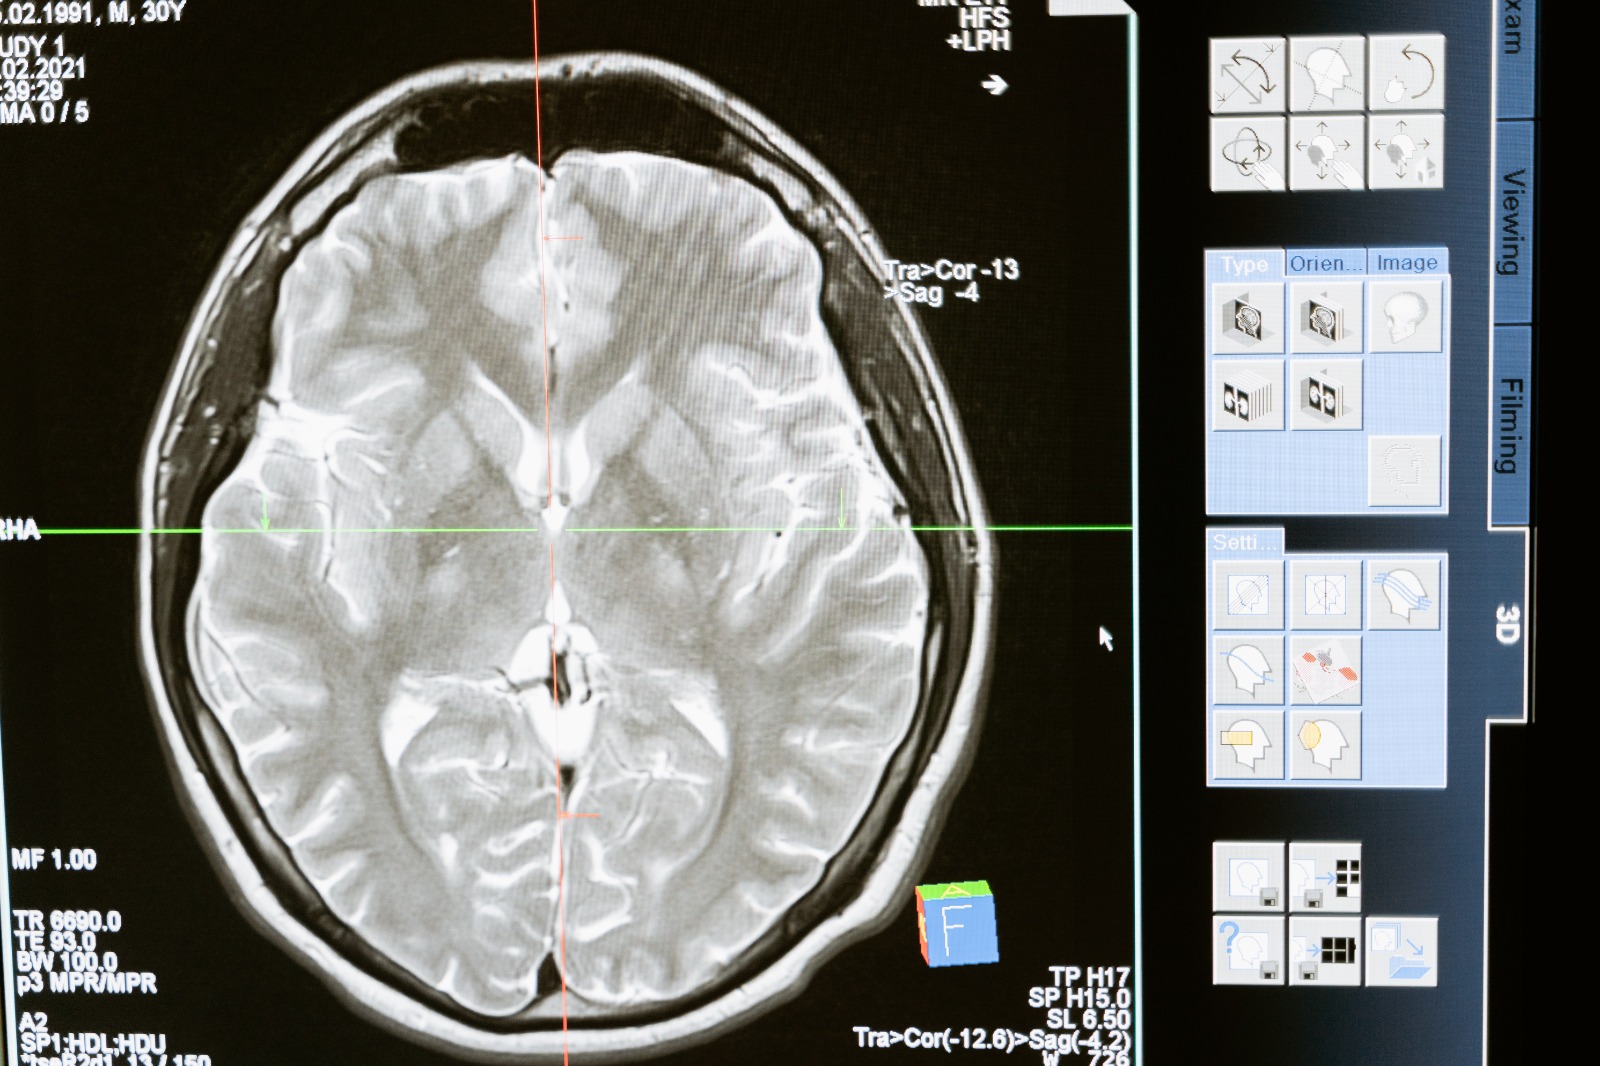

Kimimiz az kimimiz çok ama hepimiz biraz unutkanız. Bilim adamları insan beyninde bulunan bir proteinin unutkanlığa neden olduğunu belirledi.

Kimimiz az kimimiz çok ama hepimiz biraz unutkanız. Peki niye unutuyoruz? Bilim adamları insan beyninde bulunan bir proteinin unutkanlığa neden olduğunu belirledi. İsviçreli bilim adamları, bir proteinin unutkanlığa neden olduğunu tespit etti. Nature dergisindeki habere göre, Zürich kentindeki İsviçre Konfederasyonuna ait Teknik Yüksek Okulda fareler üzerinde yapılan deneylerde, Phosphatase 1 (PP1) proteininin işlevi azaltıldığında, farelerin öğrendiklerini hatırlama yeteneğini kaybetmediği gözlemlendi.